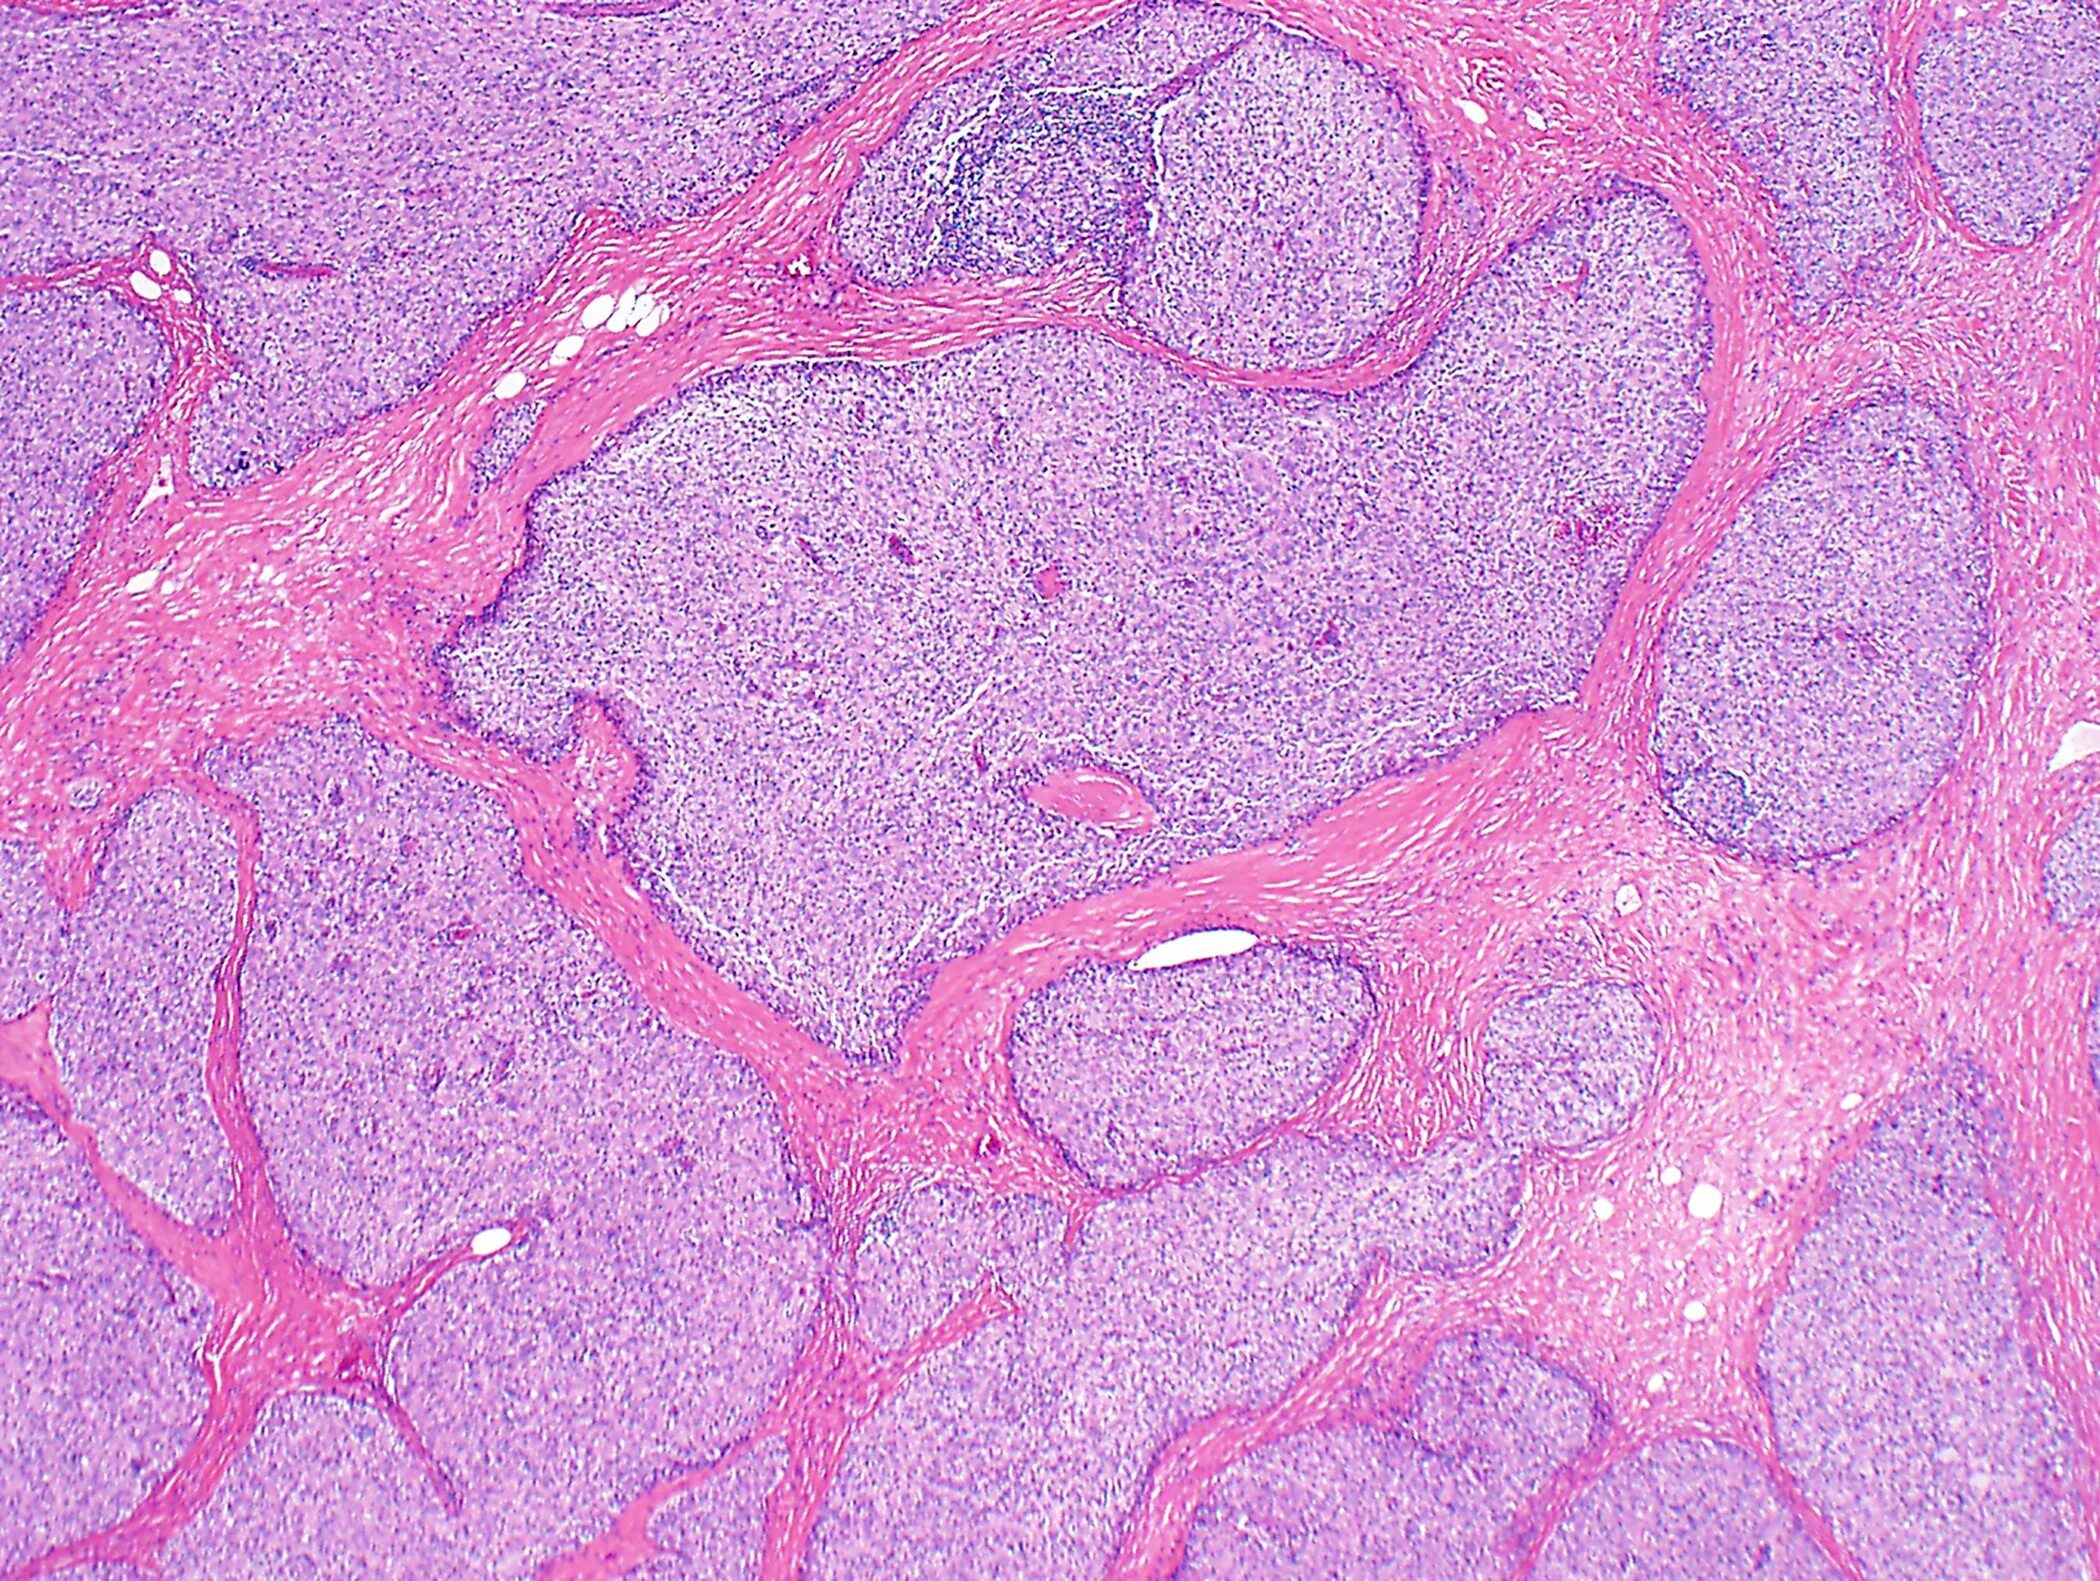

Патанат